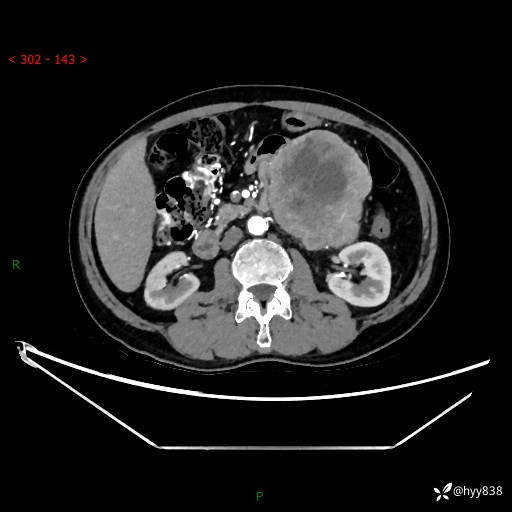

年龄:61岁

主诉:发现腹膜后肿瘤3天

腹部CT平扫+增强(动脉期+静脉期)